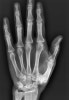

X-ray : 손 지방종(Lipoma of the hand)